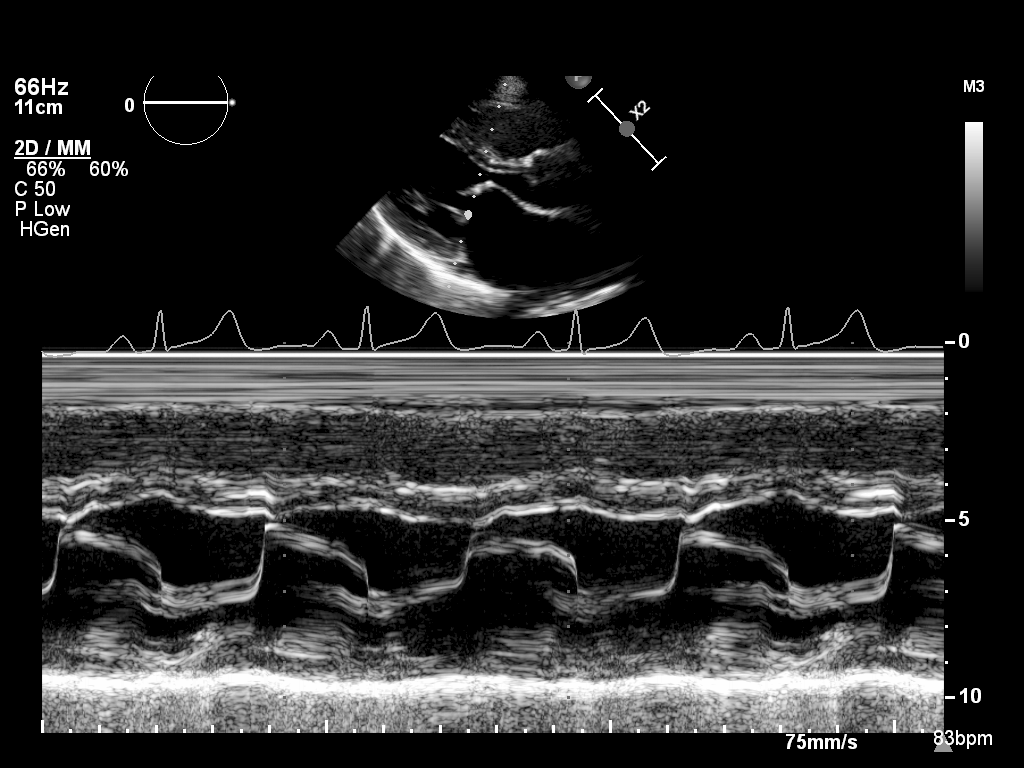

M-mode (5 views)

ImageView NameDescription

mmode-plax-lv mmode-plax-lv M-mode in PLAX focused on LV walls